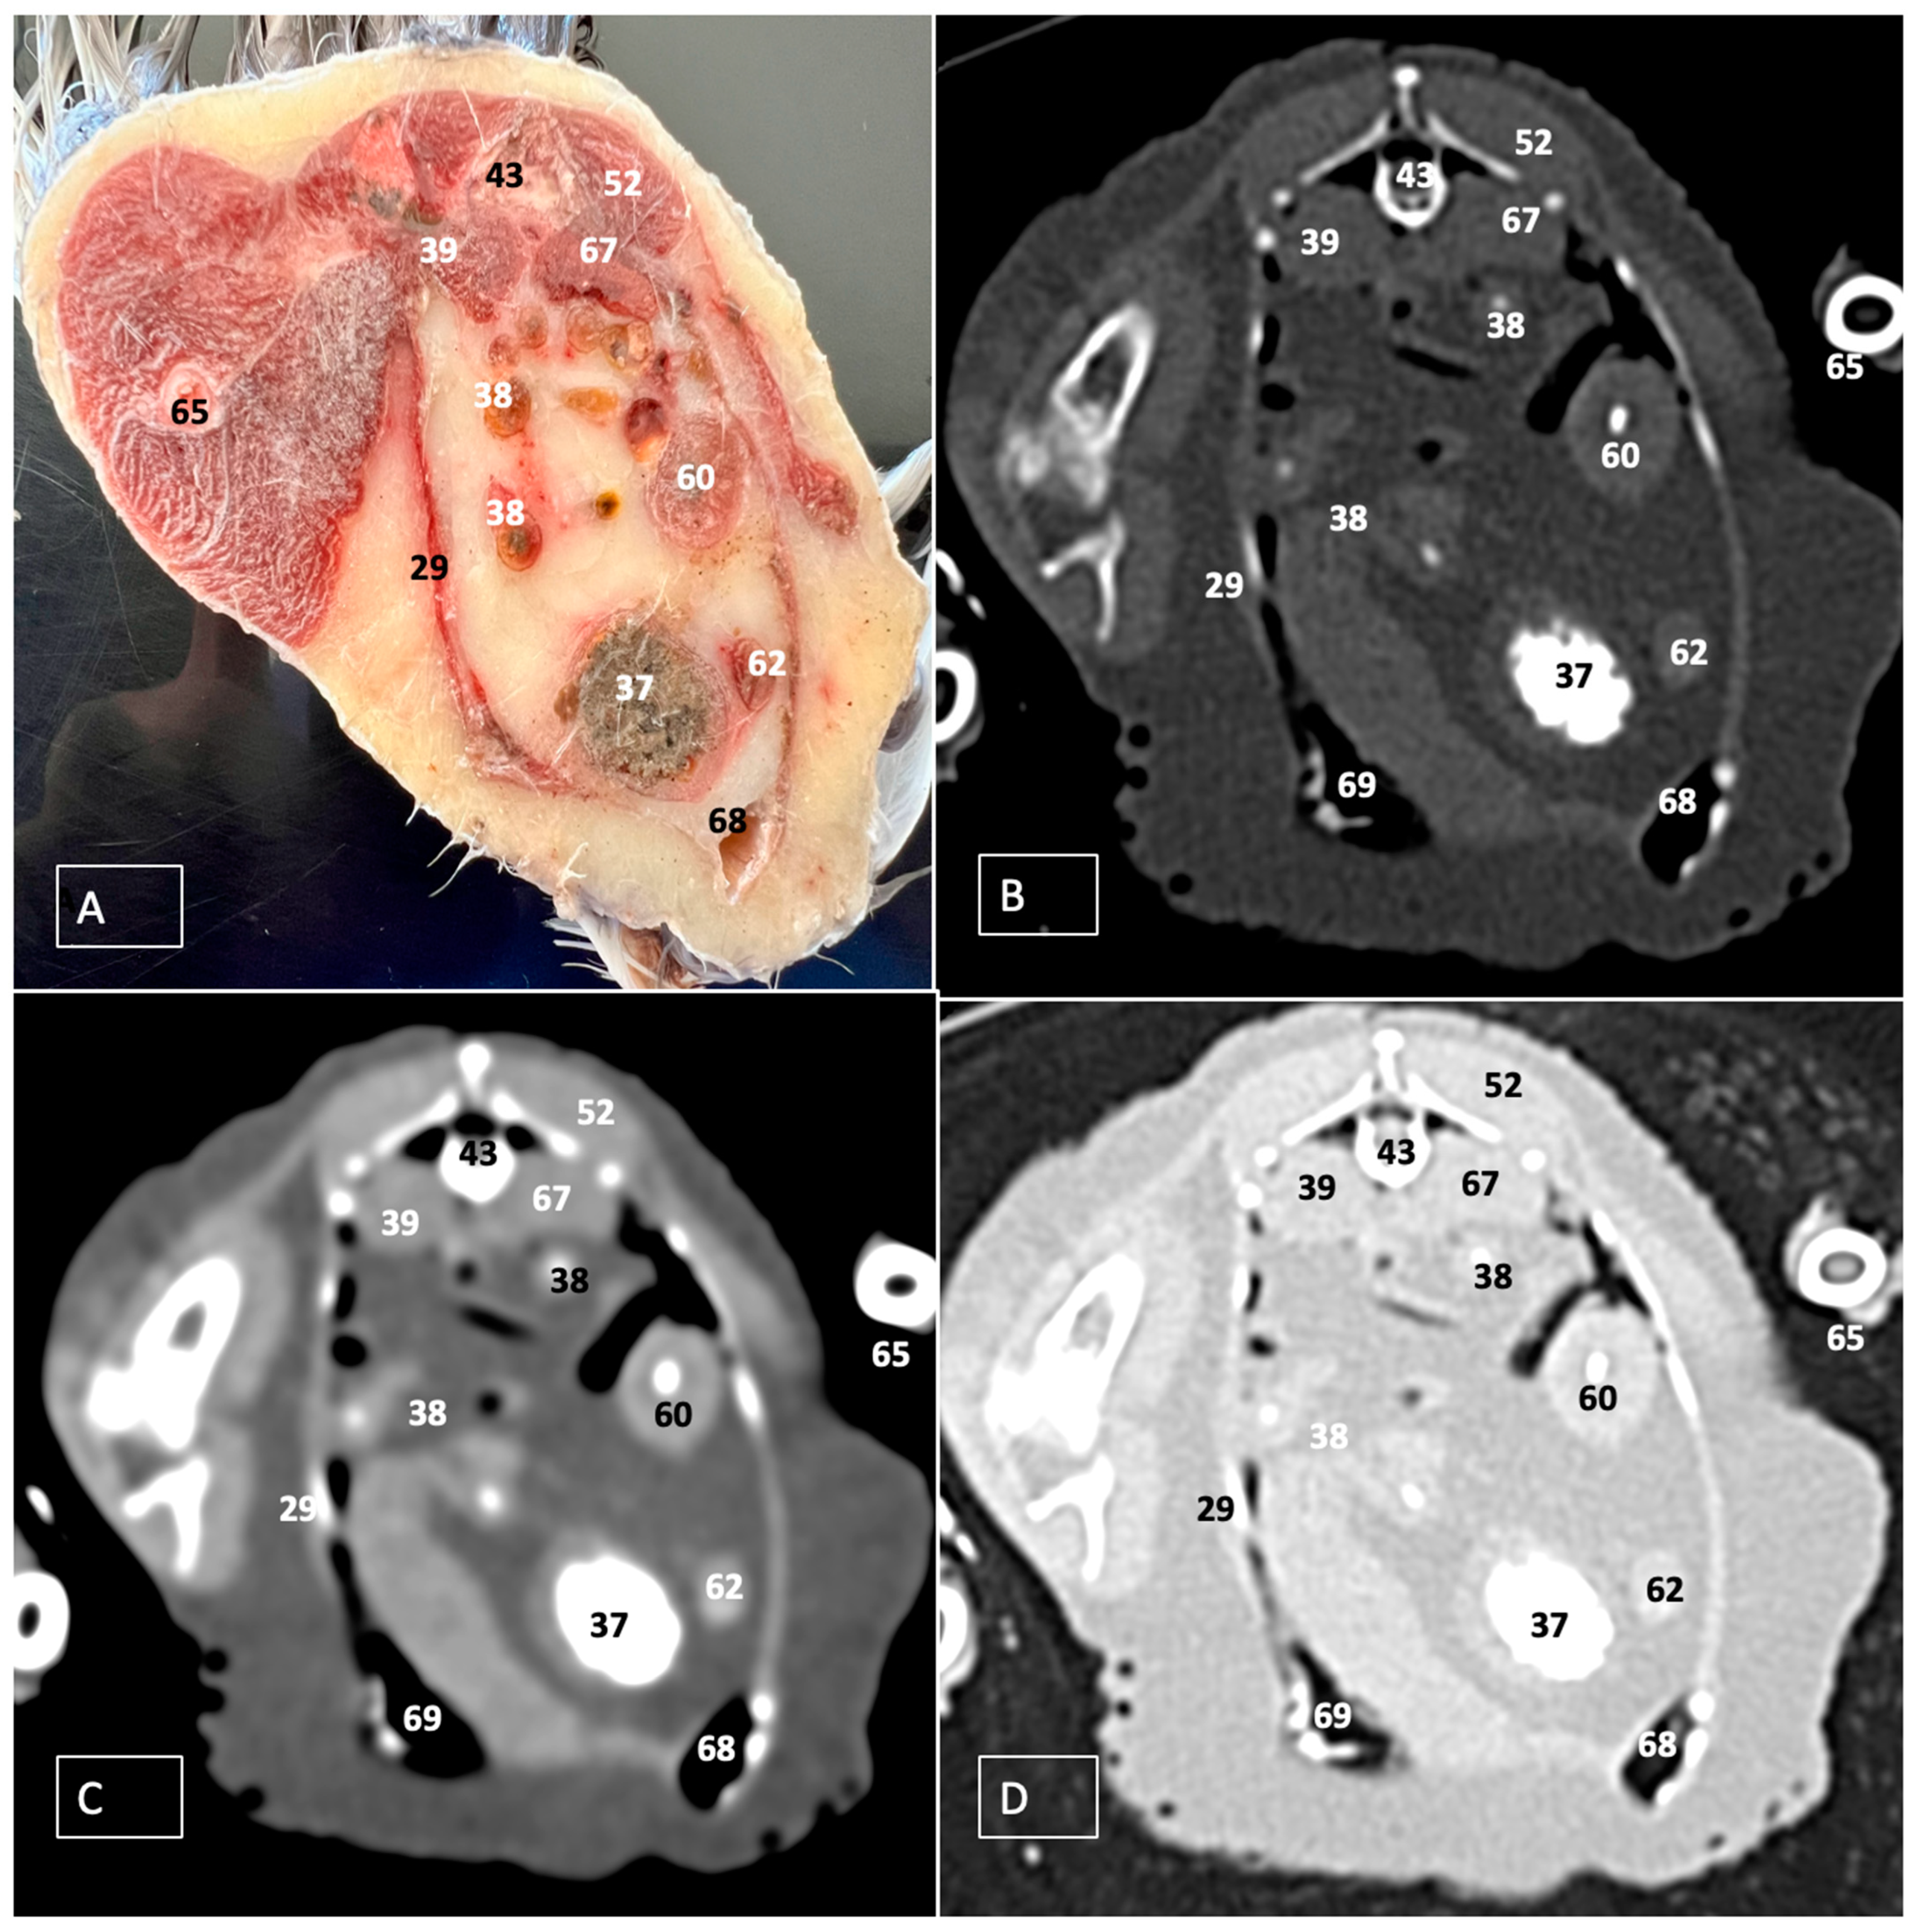

A Cadaveric Study Using Anatomical Cross-Section and Computed Tomography for the Coelomic Cavity in Juvenile Cory’s Shearwater (Aves, Procellariidae, Calonectris borealis)

3. Results

3.1. Anatomical Dissections and Cross-Sections

3.2. Computed Tomography Images